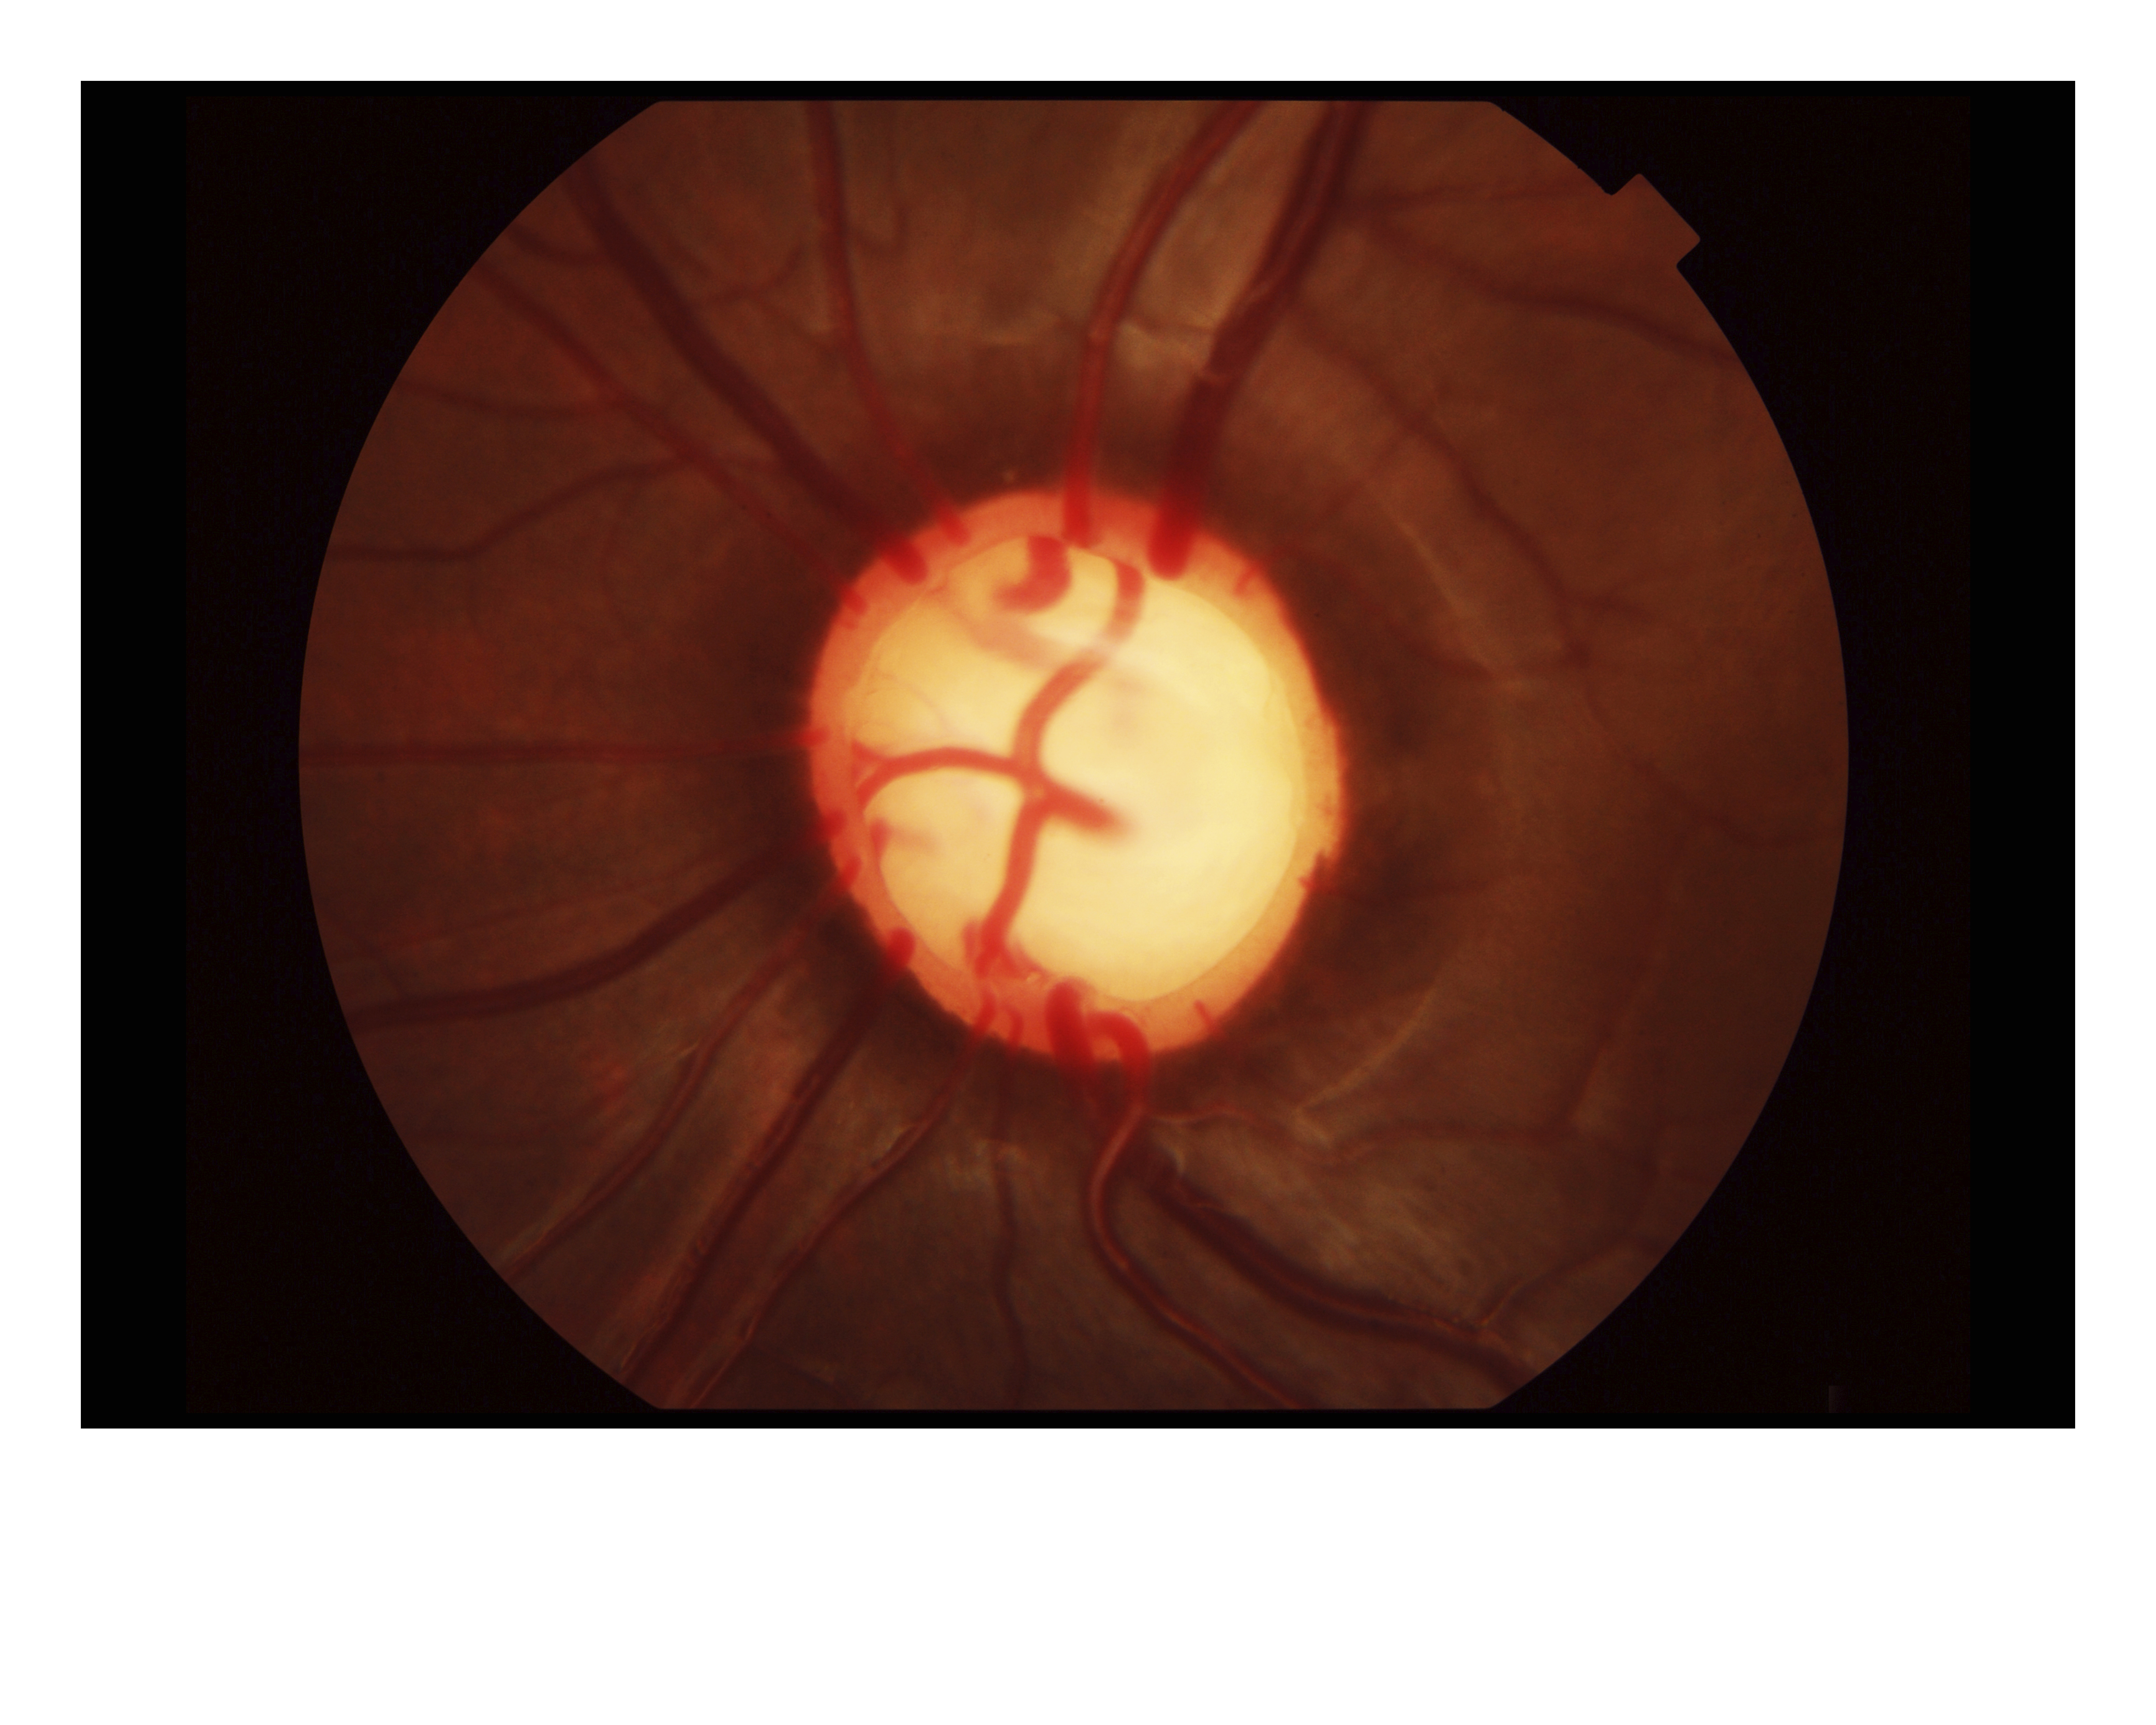

Cup Disc Presented by Govindarajan Jayaraman This photograph received First Place in the category "Fundus Photography - High Magnification" and was displayed in the 2024 OPS Exhibit. Filed Under Retina OPS Photo